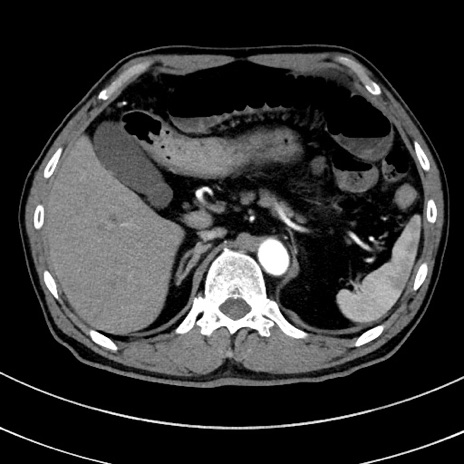

症例8(横断像)

【症例】 60歳代男性

【主訴】 黒色吐物

【現病歴】 4日前から嘔気自覚、2日前の朝食後にも嘔気あり、自分で手で嘔吐反射起こし嘔吐したところ血が混ざっていたため受診。

【既往歴】 5年前汎発性腹膜炎を伴う急性虫垂炎で手術、高血圧、前立腺肥大症、高脂血症

【身体所見】 腹部正中に手術癩痕あり 腹部平坦・軟圧痛なし膨満感あり

【データ】WBC 8400、CRP 4.54